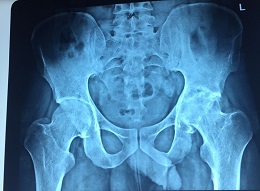

Bilateral Thr

Preop AP View

Thr 25 Yea Male

Thr 25 Yea Male 4